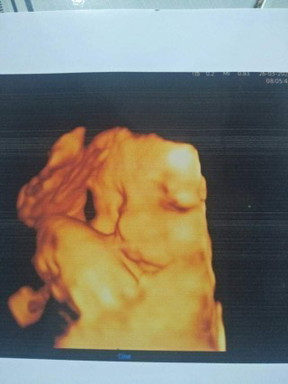

33w là 1918g nè m. vậy là đủ chuẩn ùi m nè